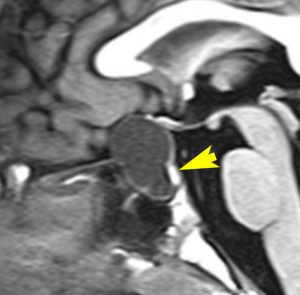

7歳の子が視力障害で発症しました。両耳側半盲という症状です。典型的な鞍隔膜下頭蓋咽頭腫です。ガドリニウム造影剤を入れないMRIでみえる,黄色い矢印の先の白い高信号は抗利尿ホルモンです。ですから下垂体機能もまだ残っていて,尿崩症はありません。視力障害が戻らないことがあるのでなるべく早く,経鼻的な手術で摘出した方がいいものです,簡単 o(^-^)o